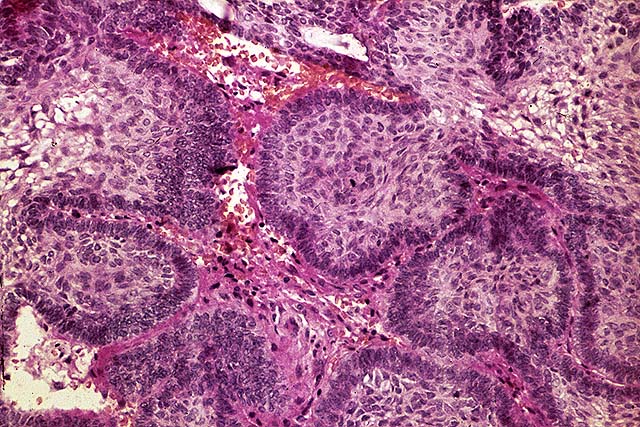

Pilomatrixoma. http://www.mrcophth.com/pathology/selftests/pilotricom.jpg